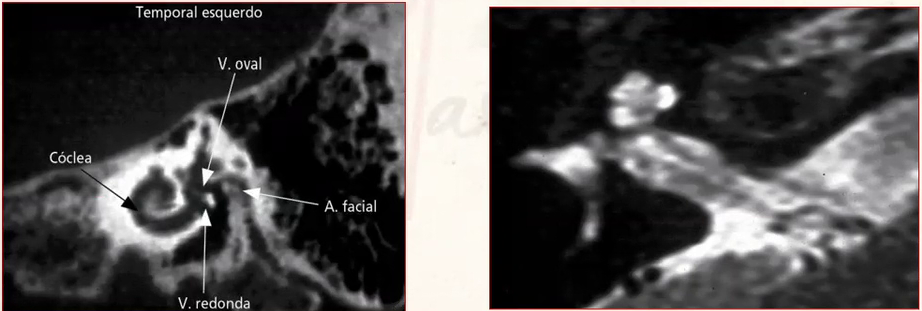

Sim. Se possível pedir ambos:

• TC é indicada para avaliação da permeabilidade coclear, pesquisa de malformações ou características sindrômicas e estudo da anatomia cirúrgica

• RM indicada para avaliação da morfologia neural (se nervo hipoplásico ou agenesia).

Estabelecer valor preditivo de sucesso ou de falha para o procedimento e avaliar prioridades. Por exemplo, pacientes com síndrome de Usher devido a chance de cegueira tem prioridade para realização do IC. Meningite pode causar ossificação rápida. Então o processo de IC também deve ser realizado precocemente. Após ossificar a cóclea se torna impossível realizar o implante (imagem).